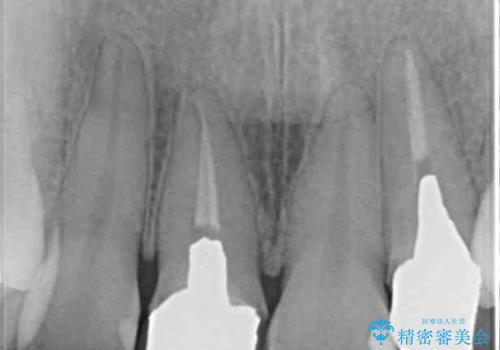

- 20年ほど前に被せた前歯のメタルボンドクラウンの色合いを気にして来院された患者様です。

2歯をオールセラミッククラウン(ジルコニアクラウン)にて補綴することとしました。

裏打ちが金属の場合、どうしても金属色を遮蔽しないとならないため、透明感のない色合いとなってしまいます。

土台の金属はグラスファイバーを含有したものに、クラウンの土台は強化セラミックとすることで、自然な前歯に仕上がりました。